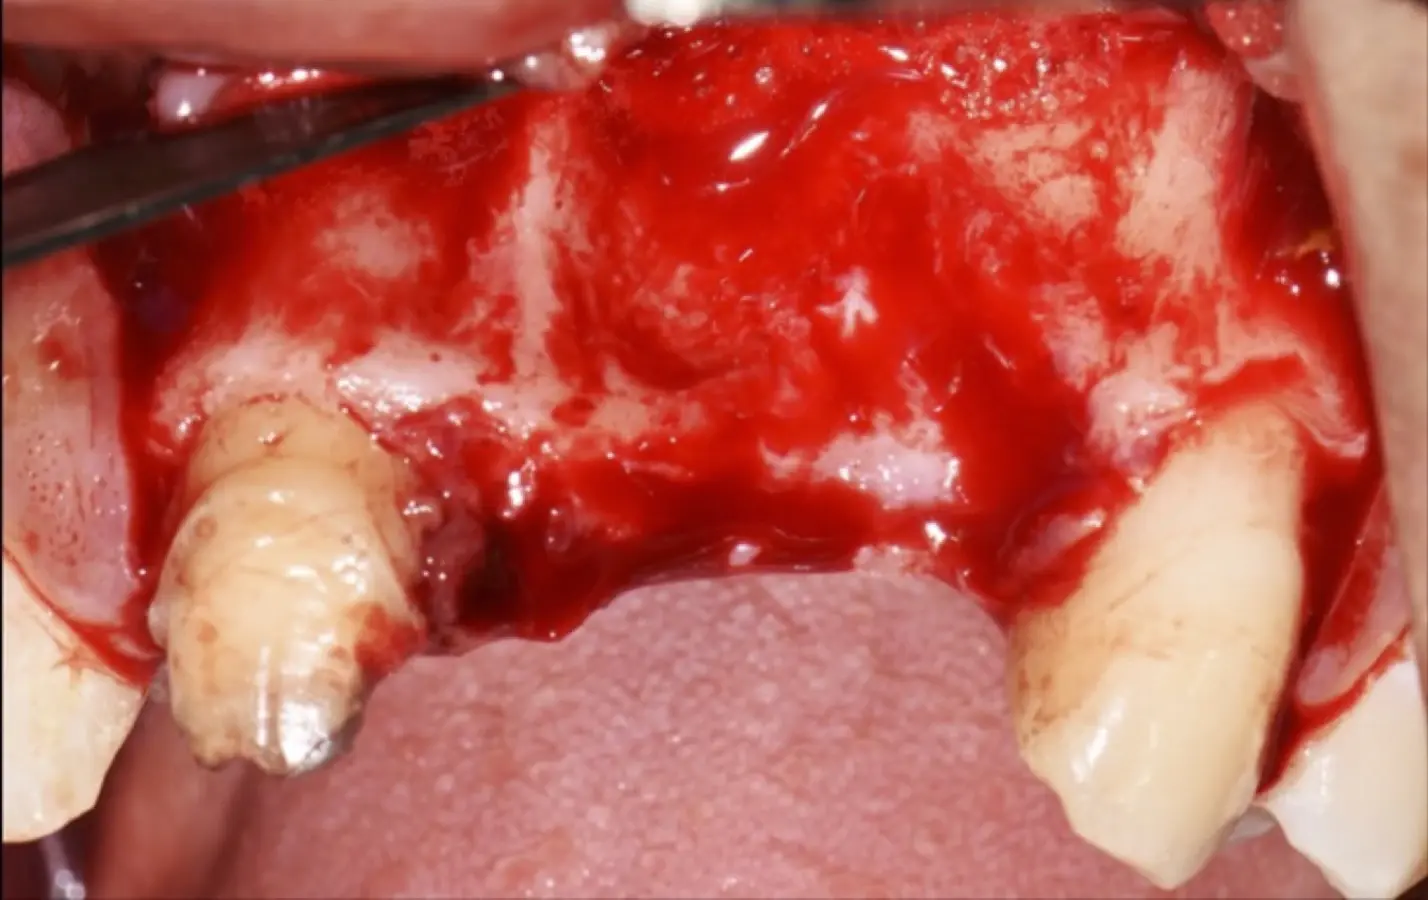

Paciente de sexo femenino de 36 años de edad, llega a la consulta por presentar una restauración protésica inadecuada. En el examen clínico se observa una restauración protésica provisional acrílica sobre las piezas 1.1 y 2.2. Adicionalmente, se aprecia recesión gingival a nivel de la pieza 2.2 y deficiencia horizontal severa de reborde a nivel de la zona edéntula correspondiente a la pieza 2.1. En la evaluación tomográfica se observa ausencia total de tabla ósea vestibular en la pieza 2.2, y se corrobora el déficit en la zona edéntula de la pieza 2.1, para lo cual se indica una reconstrucción de estructuras óseas con hueso en bloque de origen bovino y posteriormente la colocación de implantes dentales.

Figura 34. Vista frontal donde se observa deficiencia vertical del reborde óseo a nivel de las piezas 2.1, 2.2.

Figura 35. Decolado a espesor total sobrepasando la línea mucogingival (a, b).

Figura 36. Defecto óseo y severa reabsorción ósea horizontal: vista clínica (a) y corte tomográfico (b).